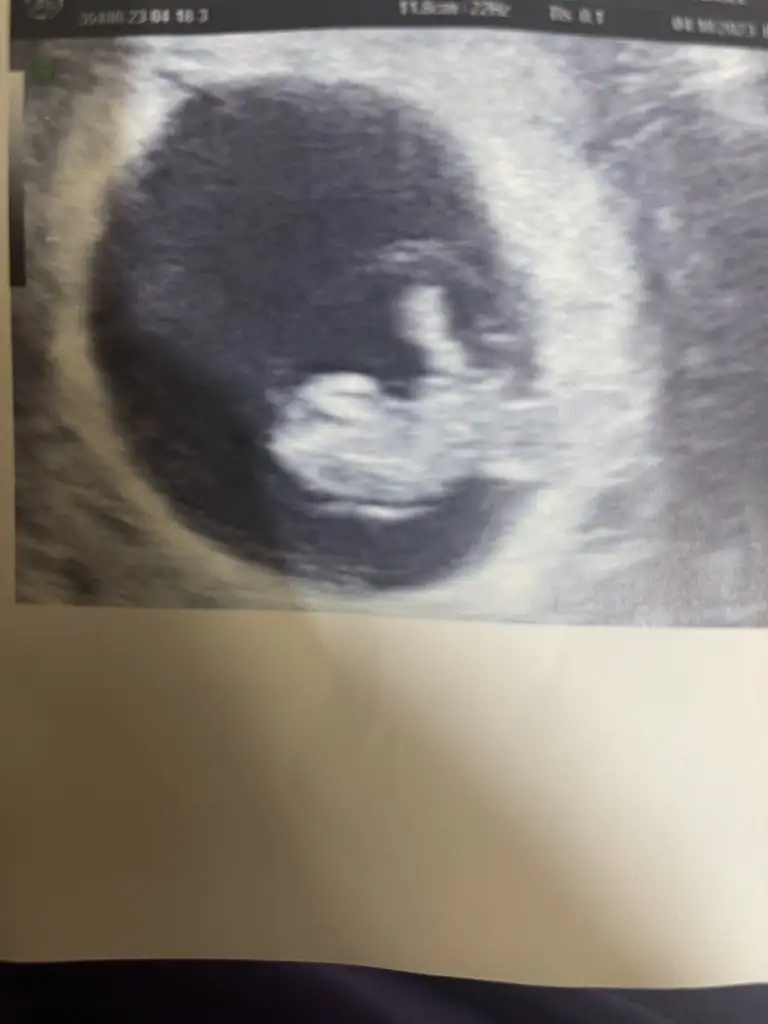

Dün attım da kimse bana yorum yapmamış

Tahminleri alabilirimmm

Eklentiler

• IMG_20230418_104953.webp

17,5 KB · Görüntüleme: 73